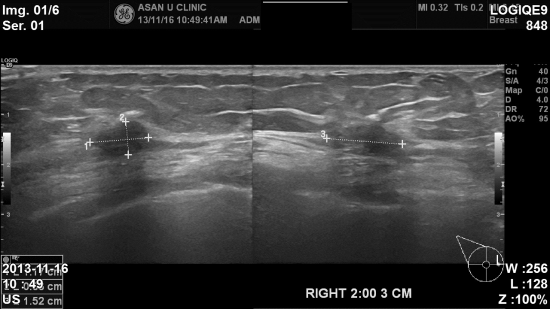

아산유외과 개원후 37번째 유방암진단.

지금껏 건강하셨던 85세 여성분입니다.

건강검진상 이상소견이 있어 본원에 의뢰되셨고

1.5cm의 우측 유방의 침윤성암으로 진단되셨습니다.

그러나 평균수명이 길어진 요즘 85세는 결코 문제되지 않습니다.

유방암의 진단에 안전한 나이는 없습니다.